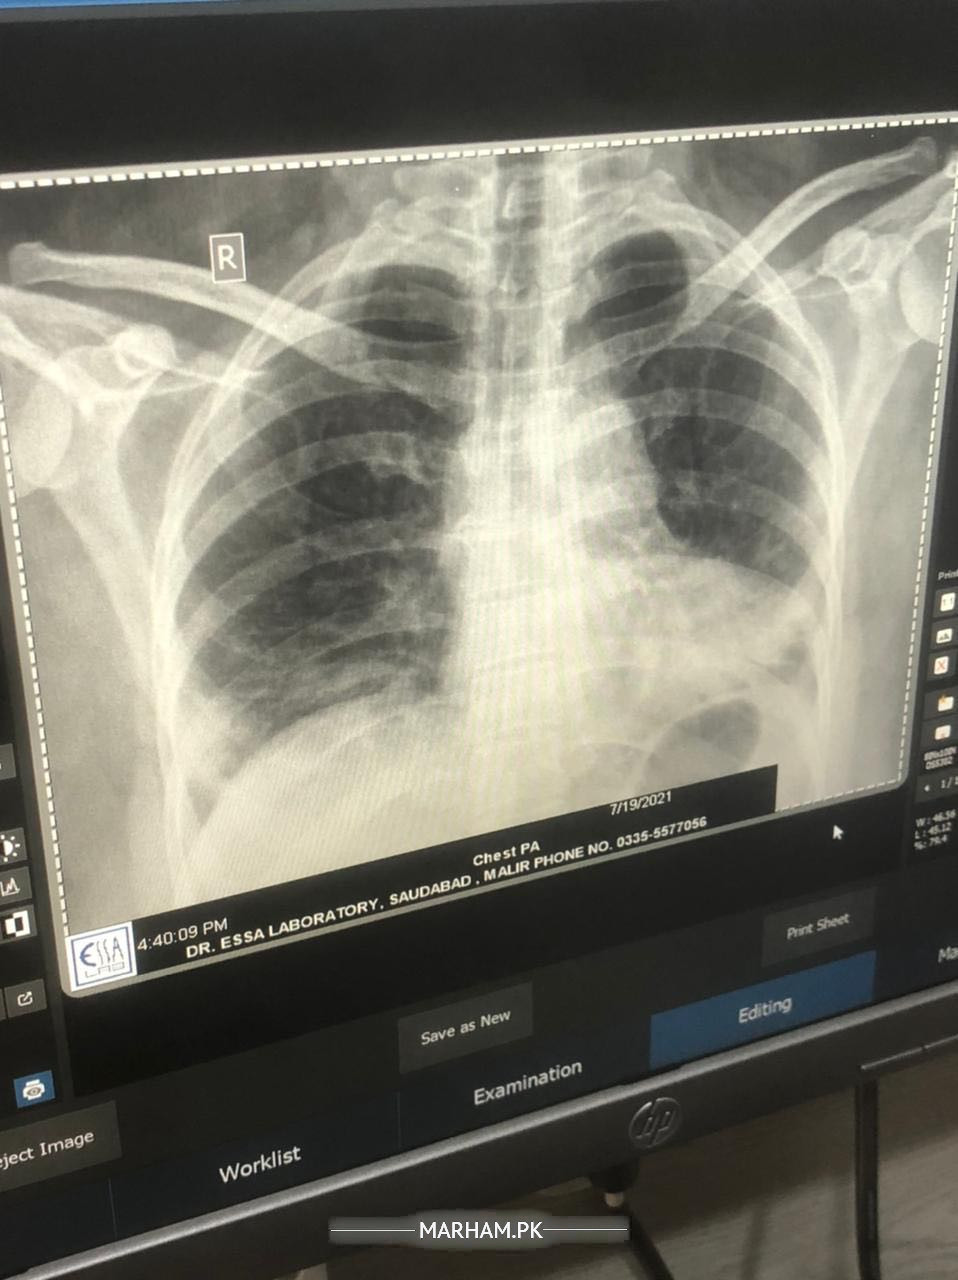

Chest x ray

4 din se meri ami ko bukhar tha lekin aj ni hua lkn aj se unhe khansi shuru hogai bht zada corona test aj karaya hmne rapid one negative aya please ap bataden k corona hai ya ni report attached

But all symptoms are COVID related